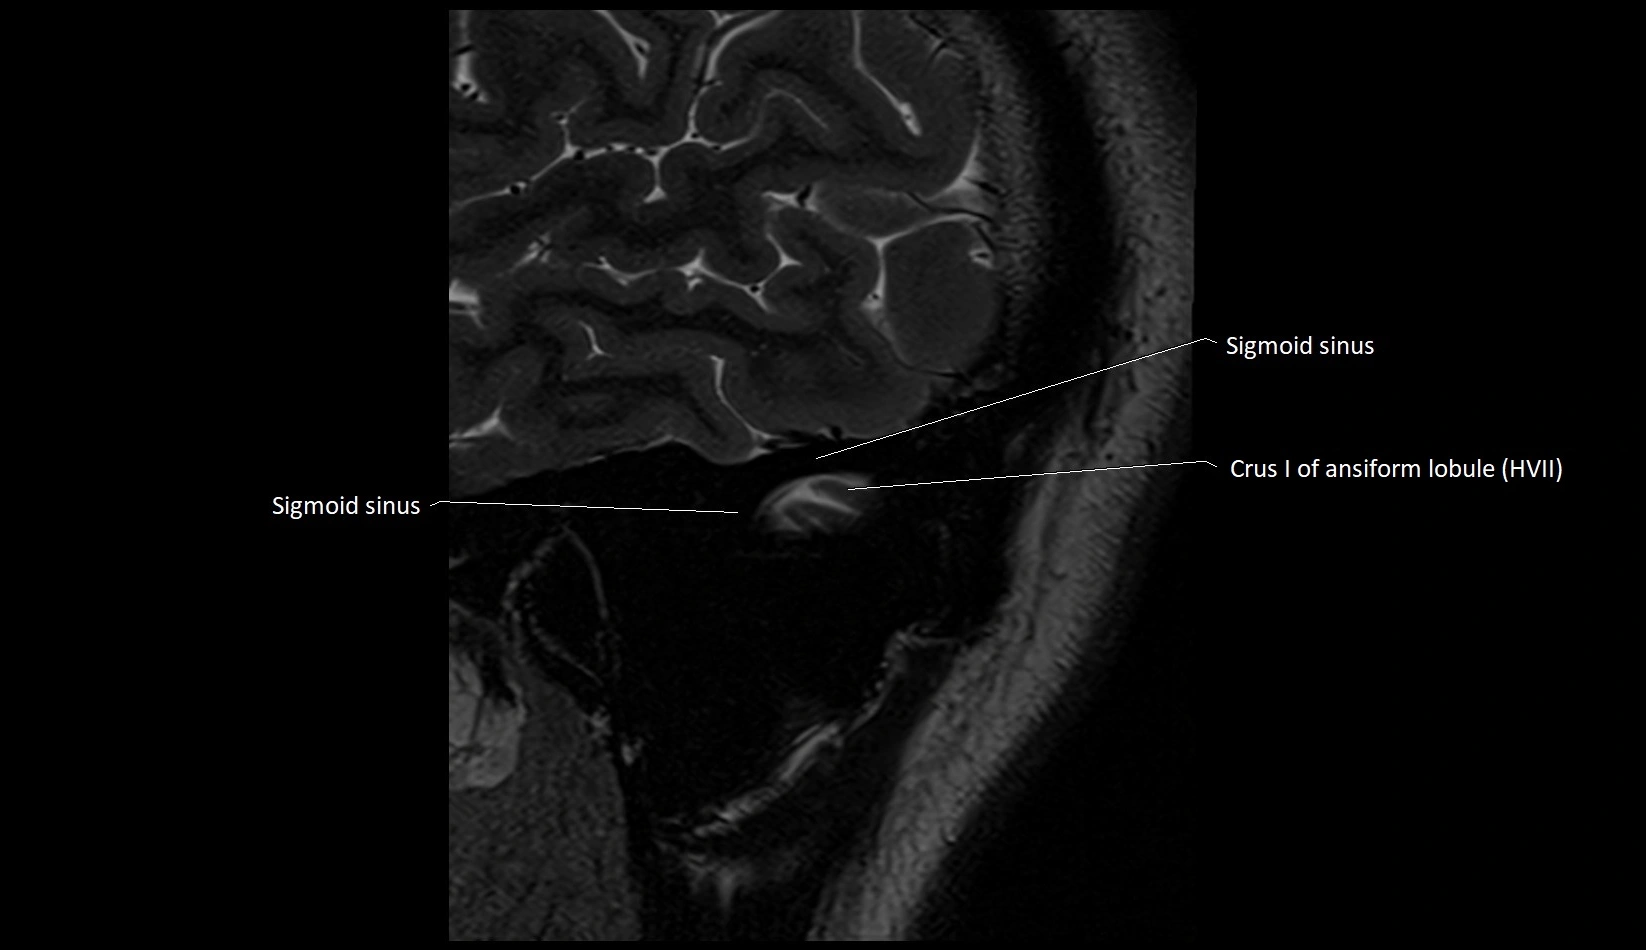

- Sigmoid sinus

- Crus I of ansiform lobule of cerebellum